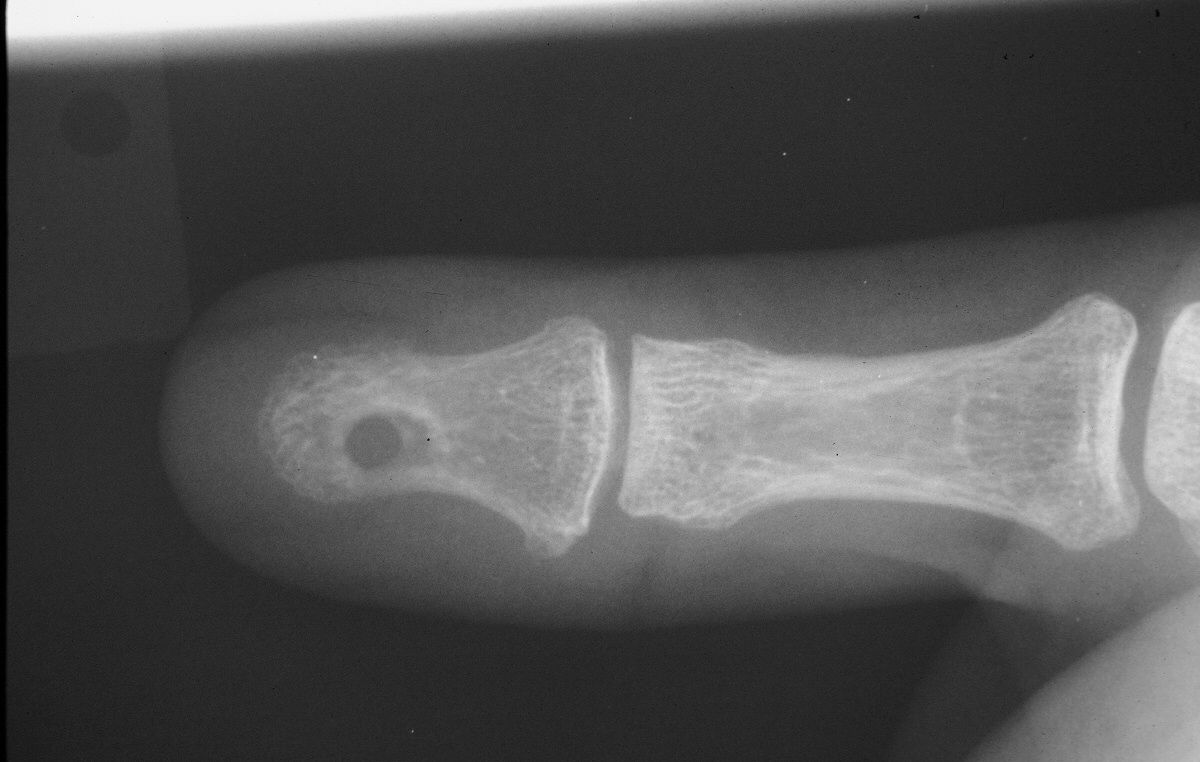

| Dorsal cortical impression

suggesting bilobed tumor. |